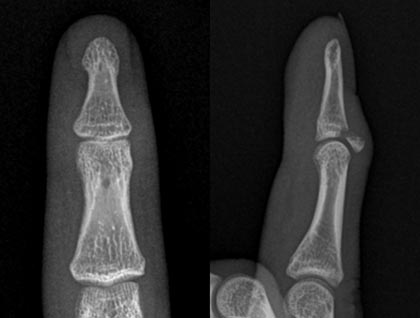

骨性槌指

伸筋腱の付着部で末節骨が骨折した状態です。指の第一関節を伸ばせなくなることが多いですが、伸ばせることもあります。治療としては、折れた骨が小さい場合は装具を用いた固定が行われていますが、折れた骨が大きい場合やずれている場合は手術が必要となることがあります。

手術は局所麻酔を行い、金属ピンなどを用いて折れた骨や指の第一関節を固定します(図8,9,10,11)。装具を用いた固定を行った場合も手術を行った場合も、約6週間の終日固定が必要となります。また、固定期間中は装具の装着状況や指の状態を評価するため、定期的な通院が必要となります。

図8.右小指の骨性槌指例